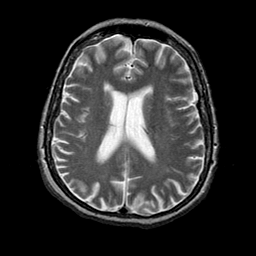

Alzheimer's disease: overlay -- Slice #15

[Home][Help][Clinical] Slice 15